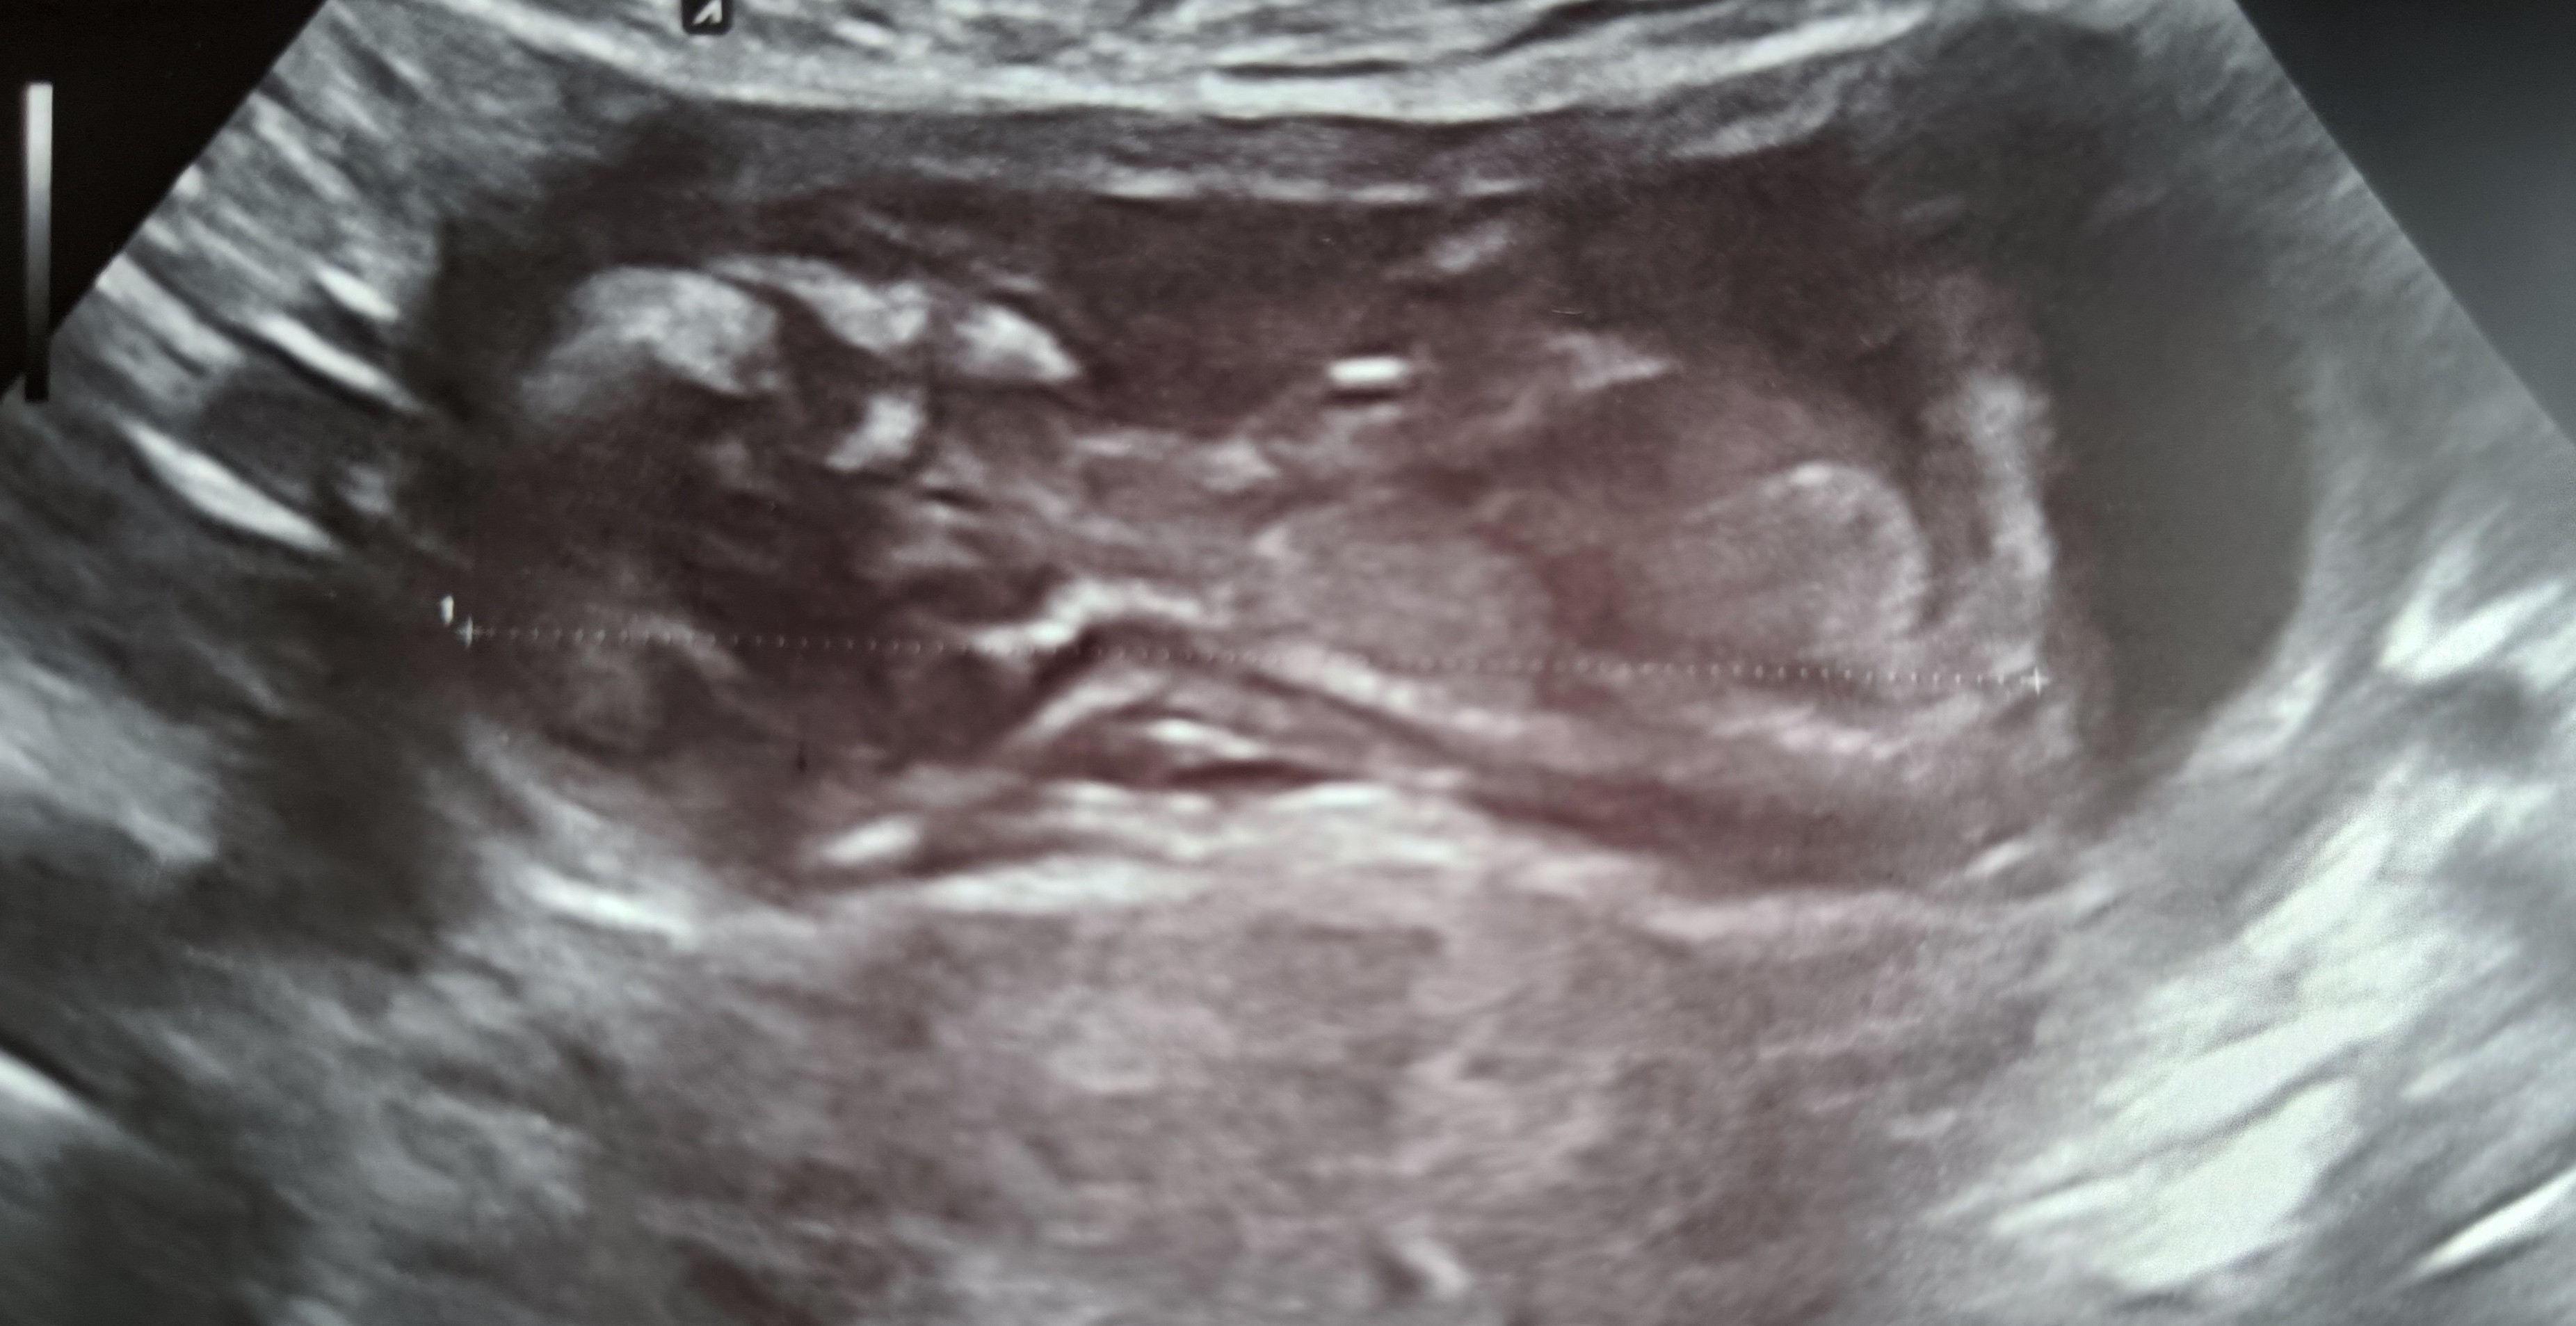

Melduje się po prenatalnych, dzidziuś zdrowy i wszystkie ryzyka wyszły niskiekolejna wizyta 8.09